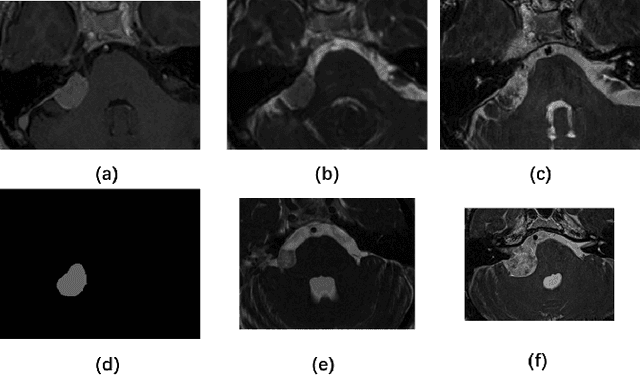

Abstract:The cross-Modality Domain Adaptation (crossMoDA) challenge series, initiated in 2021 in conjunction with the International Conference on Medical Image Computing and Computer Assisted Intervention (MICCAI), focuses on unsupervised cross-modality segmentation, learning from contrast-enhanced T1 (ceT1) and transferring to T2 MRI. The task is an extreme example of domain shift chosen to serve as a meaningful and illustrative benchmark. From a clinical application perspective, it aims to automate Vestibular Schwannoma (VS) and cochlea segmentation on T2 scans for more cost-effective VS management. Over time, the challenge objectives have evolved to enhance its clinical relevance. The challenge evolved from using single-institutional data and basic segmentation in 2021 to incorporating multi-institutional data and Koos grading in 2022, and by 2023, it included heterogeneous routine data and sub-segmentation of intra- and extra-meatal tumour components. In this work, we report the findings of the 2022 and 2023 editions and perform a retrospective analysis of the challenge progression over the years. The observations from the successive challenge contributions indicate that the number of outliers decreases with an expanding dataset. This is notable since the diversity of scanning protocols of the datasets concurrently increased. The winning approach of the 2023 edition reduced the number of outliers on the 2021 and 2022 testing data, demonstrating how increased data heterogeneity can enhance segmentation performance even on homogeneous data. However, the cochlea Dice score declined in 2023, likely due to the added complexity from tumour sub-annotations affecting overall segmentation performance. While progress is still needed for clinically acceptable VS segmentation, the plateauing performance suggests that a more challenging cross-modal task may better serve future benchmarking.

Abstract:Domain Adaptation (DA) has recently raised strong interests in the medical imaging community. While a large variety of DA techniques has been proposed for image segmentation, most of these techniques have been validated either on private datasets or on small publicly available datasets. Moreover, these datasets mostly addressed single-class problems. To tackle these limitations, the Cross-Modality Domain Adaptation (crossMoDA) challenge was organised in conjunction with the 24th International Conference on Medical Image Computing and Computer Assisted Intervention (MICCAI 2021). CrossMoDA is the first large and multi-class benchmark for unsupervised cross-modality DA. The challenge's goal is to segment two key brain structures involved in the follow-up and treatment planning of vestibular schwannoma (VS): the VS and the cochleas. Currently, the diagnosis and surveillance in patients with VS are performed using contrast-enhanced T1 (ceT1) MRI. However, there is growing interest in using non-contrast sequences such as high-resolution T2 (hrT2) MRI. Therefore, we created an unsupervised cross-modality segmentation benchmark. The training set provides annotated ceT1 (N=105) and unpaired non-annotated hrT2 (N=105). The aim was to automatically perform unilateral VS and bilateral cochlea segmentation on hrT2 as provided in the testing set (N=137). A total of 16 teams submitted their algorithm for the evaluation phase. The level of performance reached by the top-performing teams is strikingly high (best median Dice - VS:88.4%; Cochleas:85.7%) and close to full supervision (median Dice - VS:92.5%; Cochleas:87.7%). All top-performing methods made use of an image-to-image translation approach to transform the source-domain images into pseudo-target-domain images. A segmentation network was then trained using these generated images and the manual annotations provided for the source image.